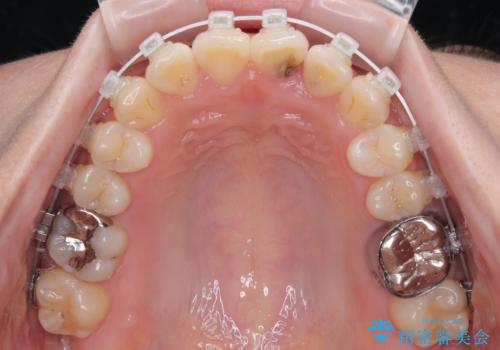

診察の結果、上下の前歯部に**叢生(そうせい/歯のガタガタ・重なり)**が認められました。

特に上の前歯にはねじれや重なりがあり、審美的にも清掃性にも影響している状態でした。

治療方法としては、装置の目立ちにくさと費用面のバランスを考慮して、プラスチック製のクリアブラケットとメタルワイヤーを組み合わせた矯正装置を使用することにしました。

また、上顎前歯の重なっていた部分にはむし歯が見つかり、治療中に適切な処置を行っています。